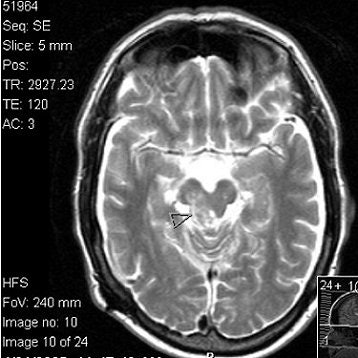

![]() |

Above, T1-weighted postcontrast axial image from the MRI series undergone by Dena Schlosser. Below, an axial diffusion-weighted image. Schlosser's neurologist examined Schlosser after her first trial and, based on the MRI exam, testified that midbrain injuries could cause visual hallucinations. Schlosser had previously told psychiatrists that she believed God wanted her to cut off her child's arms, as well as her own arms, legs, and head (Dallas Morning News, April 3, 2006). Images courtesy of David K. Haynes, Attorney at Law.